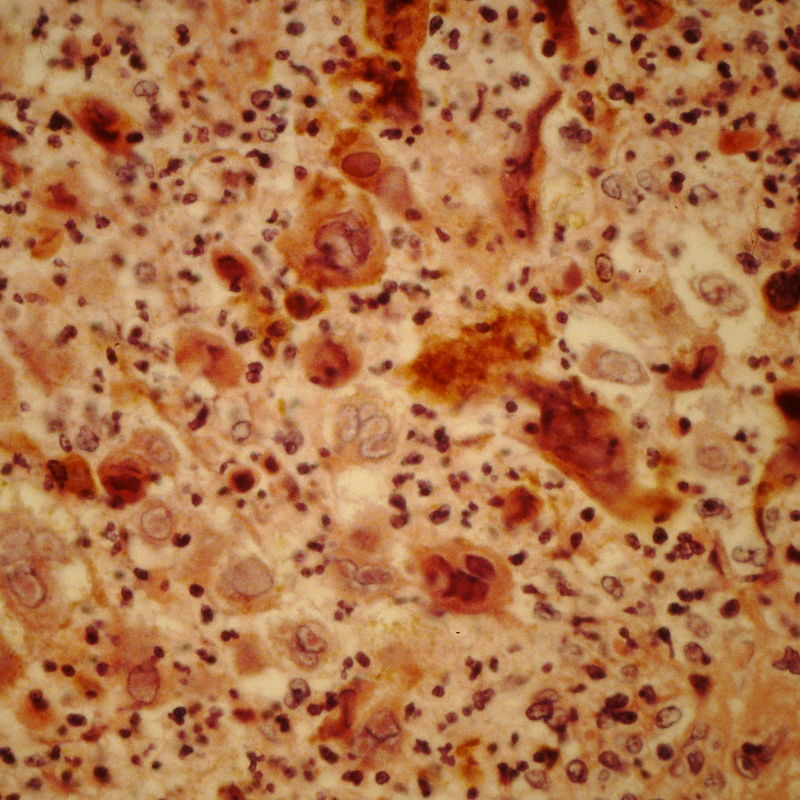

Professor Borner is a leading scientist in the field of apoptosis research. His career and activities include the following stations: 2014-present Director of the International Master Program in Medical and Biological Sciences (IMBS) between the Universities of Buenos Aires and Freiburg 2013-present Professor and Tutor in Biology, Psychology and Environmental Sciences for the Business and Administration study track of the California Miramar University (CMU) in Nairobi, Kenya (50% lectures, 50% online/e-learning tutoring).